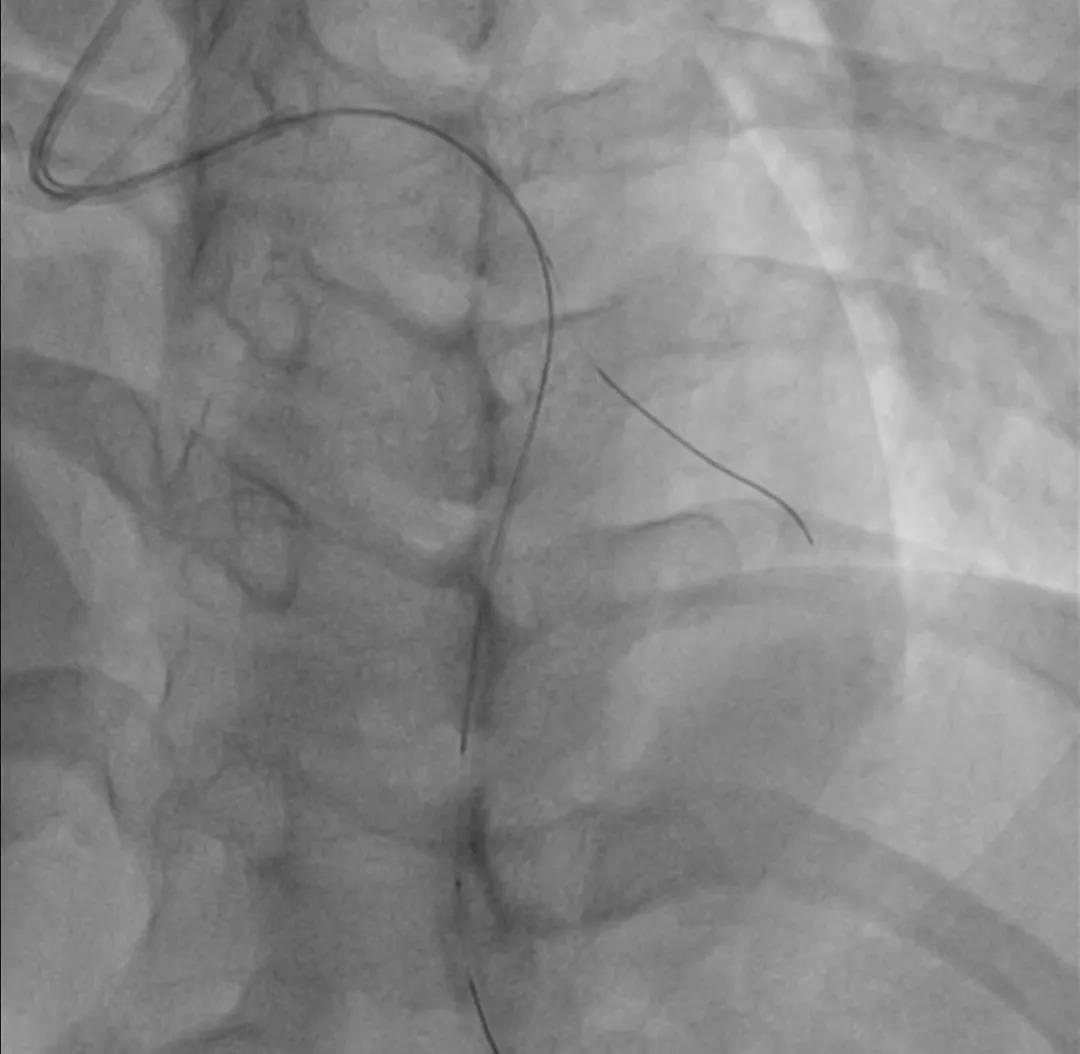

单支病变 LAD-CTO策略

两段闭塞 J-CTO score = 2(blunt tip/bending angle>45°)

无明显钙化,闭塞节段较短,首选对侧造影支持下正向策略

EBU3.0+Finecross微导管+XT-R做初始尝试

必要时升级导丝硬度

注意第二段闭塞成角

IVUS评估后决定是否行DEB